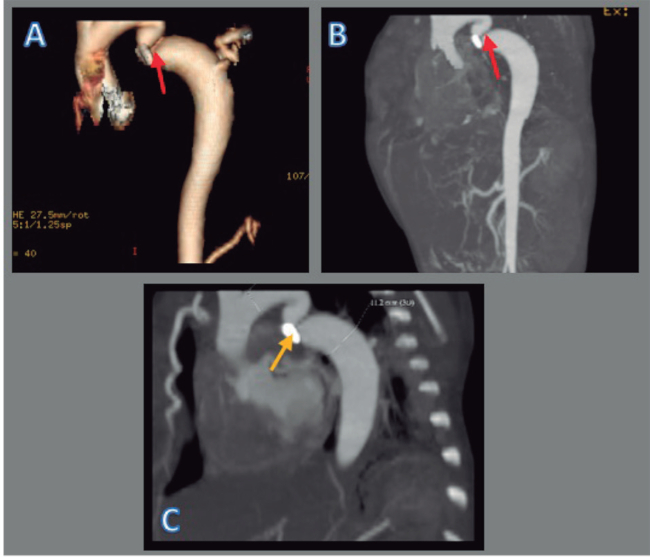

Posteriormente, se logra la extubación y el paciente pasa a cuidados intermedios donde permanece estable durante 8 h aproximadamente. De forma súbita, presenta deterioro cardiovascular y respiratorio (score Downes 8) que requiere nuevamente VMA con parámetros elevados. Debido a la abrupta aparición de la sintomatología mencionada, se solicita un ecocardiograma que reportó una posible CoAo, por un gradiente de presión de 61 mmHg más corrida diastólica y presión pulmonar de 37 mmHg (Figura 1 A-C). Se solicita una angiotomografía contrastada de tórax, que reportó una estenosis grave de la aorta descendente después de la arteria subclavia izquierda con discreta dilatación posestenótica de la aorta descendente (11 mm), tortuosidad y dilatación de las arterias mamarias internas derecha e izquierda, además de las arterias intercostales (Figura 2 A-C). A los 11 días de vida, el servicio de cirugía cardiotorácica realiza una coartectomía ampliada más anastomosis término-terminal sin complicaciones.